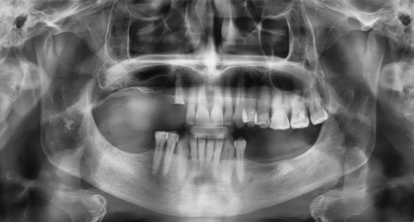

Lo scopo del seguente case report è quello di valutare il successo clinico nella riabilitazione implanto-protesica utilizzando una nuova geometria implantare ADVANGTB SINUS LIFT, in un sito edentulo del mascellare superiore posteriore atrofico adiacente al seno mascellare. Tre diversi Impianti endossei ADVAN sono stati inseriti in un paziente parzialmente edentulo e che presentava altezze crestali residue differenti.